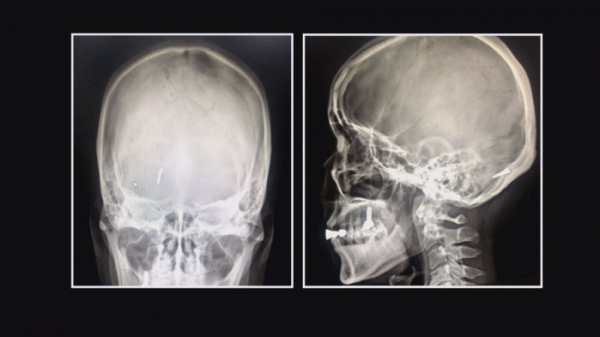

제작진은 특별한 아내를 소개하고 싶다는 제보를 받았다. 몸속, 그것도 머릿속에 무언가가 들어있다고 한다. 병원에서 찍은 엑스레이 사진에는 하얀 물체가 선명하게 보인다. 머릿속 의문의 물질과 함께 지내고 있는 문은주(55) 씨가 오늘의 주인공이다.

문 씨는 20여 년 전, 교통사고를 당했다. 다행히 큰 부상은 없었지만 CT 촬영을 하다가 머릿속에 금속 파편이 있다는 이야기를 들었다. 깜짝 놀랐지만 오히려 수술이 위험할 수 있고, 일상생활에 별다른 불편함이 없었기 때문에 수술하지 않고 지냈다고 한다.

언제 어떻게 머릿속에 금속이 들어갔는지 여전히 의문이다. 현재 문 씨의 상태를 알아보기 위해 엑스레이와 CT 촬영을 해보았다. 그 결과 놀라운 사실이 밝혀졌다. 두개골을 뚫고 뇌에 박혀있는 의문의 물질에 검사를 시행한 의사 역시 놀라워했다.